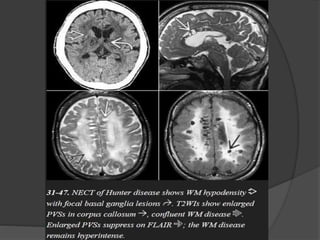

Mucopolysaccharidoses

Lysosomal storage disorders characterized by incomplete degradation and

progressive accumulation of toxic glycosaminoglycan (GAG) in various

organs.

The major features of these disorders are

• Macrocephaly,

• Enlarged perivascular spaces, and

• Pachymeningopathy.

Imaging

Macrocephaly

NECT scans show an enlarged head, often with metopic "beaking".

Progressive hydrocephalus and atrophy can be present.

Enlarged Perivascular Spaces

A striking sieve-like cribriform appearance in the posterior cerebral WM

and corpus callosum is characteristic and is caused by numerous dilated

PVSs (peri-vascular spaces)- also called as "Hurler holes," these

enlarged PVSs are typical of both Hurler and Hunter diseases. They are

much less common in the other MPSs.

NECT scans may show decreased density with multifocal CSF-like

hypodensities in the WM and basal ganglia.

T2 scans show CSF-like hyperintensity in the enlarged PVSs. The

surrounding WM may show patchy or confluent hyperintensity. The PVSs

themselves suppress completely on FLAIR.

The enlarged PVSs do not "bloom" on T2* and do not enhance following

contrast administration.

Pachymeningopathy

Thickened meninges can compress the medulla or upper cervical cord.

Odontoid dysplasia and a short C1 posterior arch—common in the MPSs—

can exacerbate the craniovertebral junction stenosis, causing progressive

myelopathy.

A lumbar gibbus with a "beaked" L1 vertebral body is common in Hurler